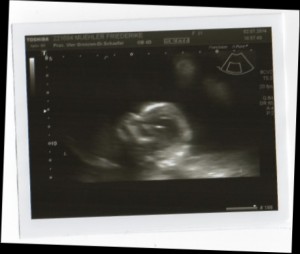

Heute gab es ein Fotoshooting der besonderen Art beim Opa auf Arbeit. Sein Kollege, der stellvertretende Chefarzt der Kinderklinik und gleichzeitig Guru des Ultraschalls, hatte sich bereit erklärt den werdenden Eltern noch ein paar aktuelle Fotos zu machen. Leider gab es kein 3D, aber dafür ein paar süße Fotos und vor allem Videos unseres Sohnemannes, der sich die ganze Zeit über ruhig verhielt und sich der Kamera, äh dem Schallkopf stellte.